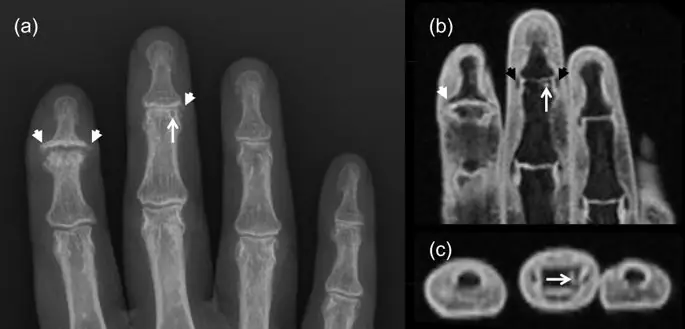

CR дает двумерную картину костных изменений, таких как остеофиты, эрозии, кисты и склероз, а также сужение суставного пространства (JSN) в качестве косвенной меры потери хряща (рис. 1).

Обычная рентгенография (CR) и магнитно-резонансная томография (MRI) (корональные / осевые T1-взвешенные жиросжатые изображения) правой руки. Как CR (a), так и MRI (b, c) показывают тяжелый остеоартрит с остеофитами (белые стрелки) и центральный коллапс суставной пластинки во 2-м дистальном межфаланговом суставе (DIP). И МРТ, и CR показывают сильное сужение суставного пространства в 3-м DIP-суставе. Остеофиты легче увидеть на КР, тогда как МРТ показывает коллатеральные связки (черные стрелки). CR показывает кистоподобное повреждение (белая стрелка), которое при МРТ кажется эрозией (то есть кортикальным разрывом в осевой плоскости).